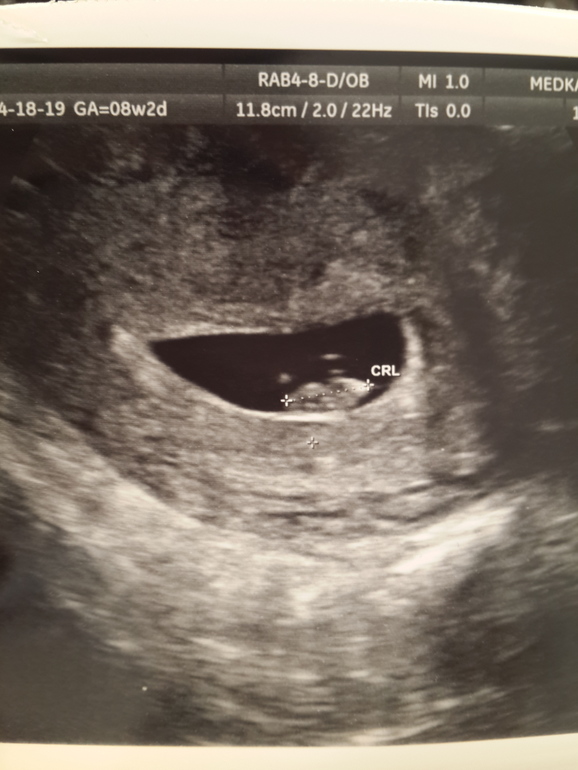

ЛичноеУииииии......моя любовь)))))) 11мм. Чсс 146уд/мин))))))) по месячным 8недель и 2 дня. По размеру ляли 7нед.и 3дня))))))) всё хорошо. Слава Богу. Угрозы нет)))))) следующее узи (скрининг) в конце мая. На 13 неделе. Кому нибудь на таком сроке угадывали с полом малыша???? Мне на 12 неделе сыночка, девочкой назвали)))))) и фото моей малютки.